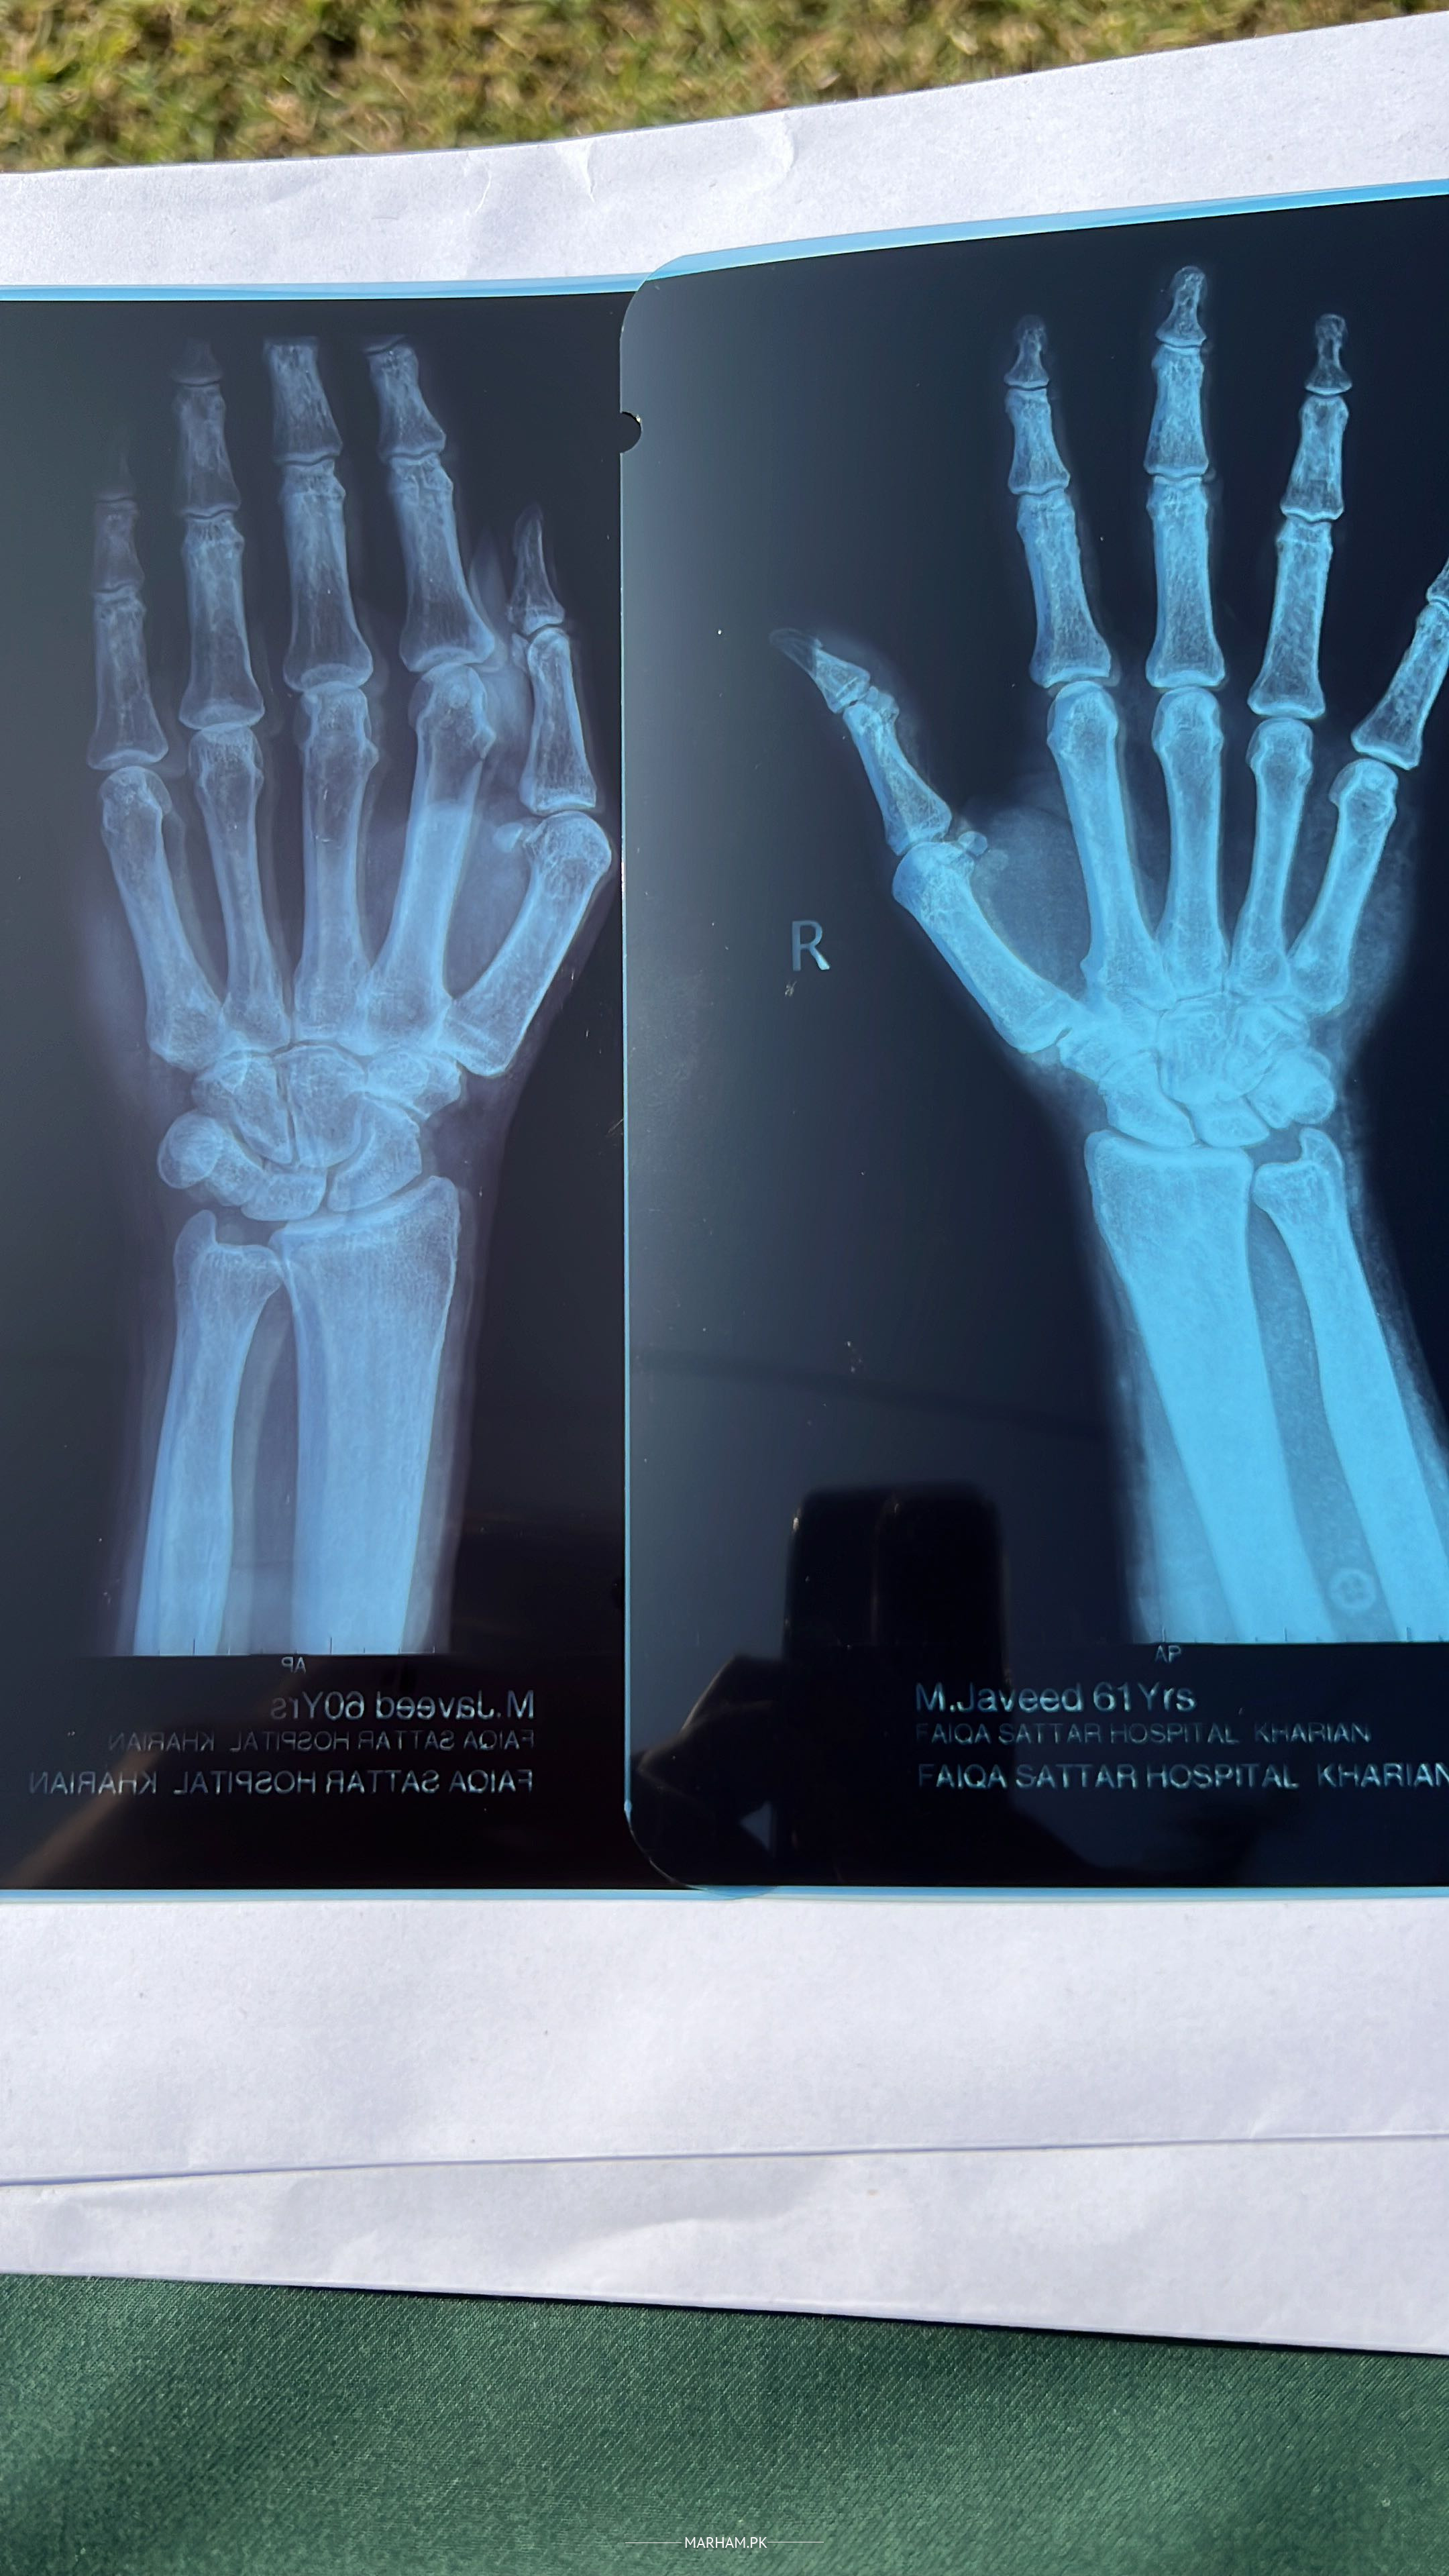

From www.marham.pk

Ask a Physiotherapist Online for Wrist Joint Pain How To Treat Wrist Joint Pain From strains and sprains to tendonitis and carpal tunnel syndrome, wrist pain is all too common. How is wrist pain treated? Treatment for carpal tunnel syndrome. A person’s wrist may hurt due to various reasons, such as a sprain, carpal tunnel syndrome, or arthritis. But relief is possible by doing wrist pain exercises and stretches, says. Which treatments you’ll need. How To Treat Wrist Joint Pain.